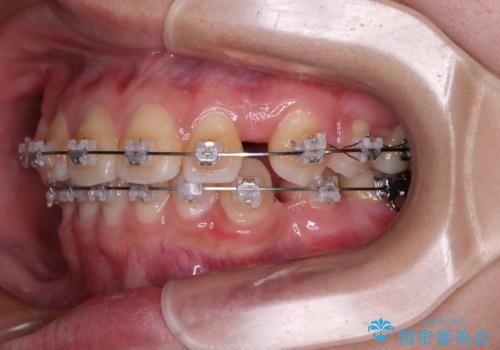

- 矯正装置

- クリアブラケット

- 転勤により東京へ移られることになり転院先を探されていた患者様です。ワイヤー矯正の途中での急な転勤なうえ、今後2~3年以内に再度転勤になる可能性もあるというご事情でした。

そのため、限られた期間内に効率よく治療を完了するために、「抜歯スペースの確実な閉鎖」「深い噛み合わせ(過蓋咬合)の改善」の2点を主軸とした治療計画を立てました。

結果的に1年半で、再度転勤になる前に治療を終えることができました。